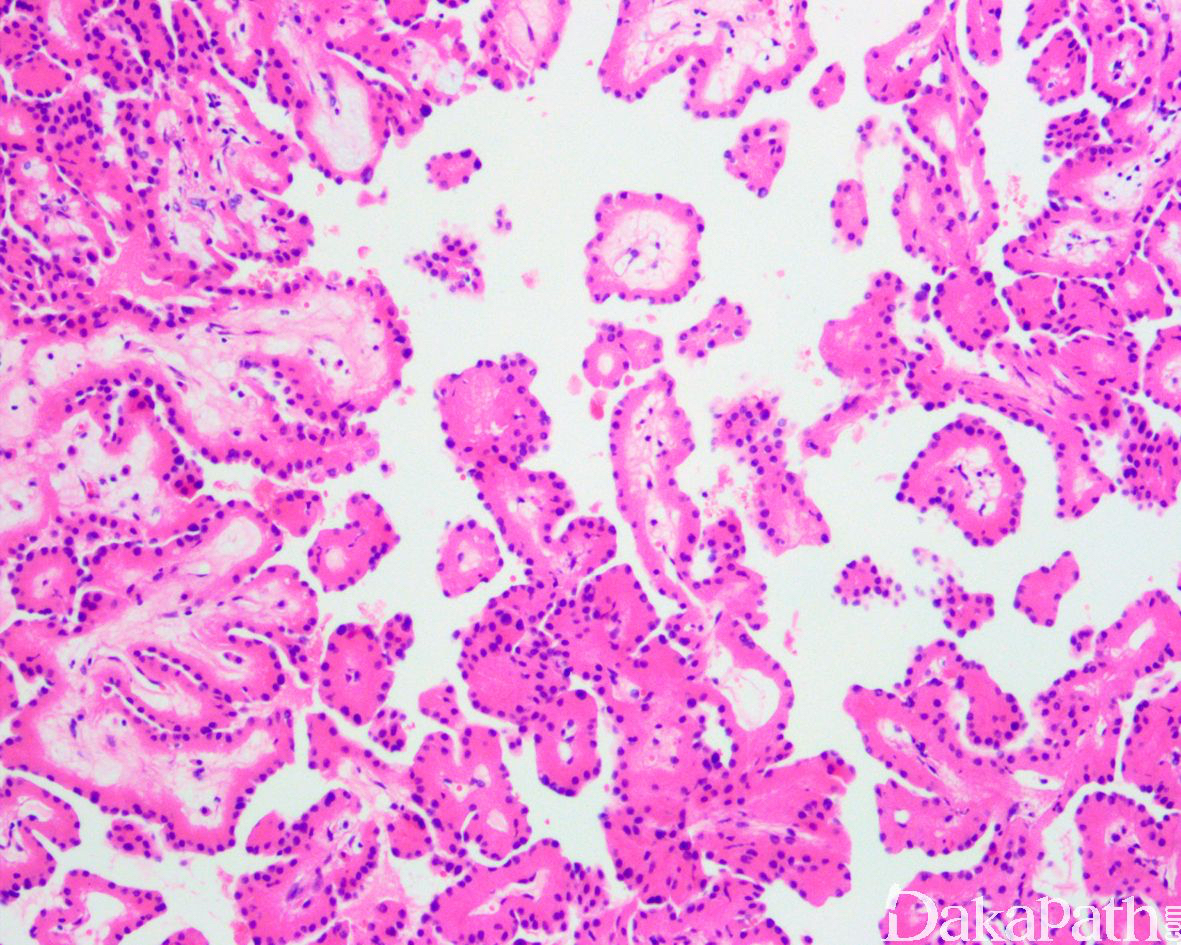

低倍镜下肿瘤主要由具有纤维血管轴心纤细的乳头状结构组成,伴有多少不等的管状结构;偶尔可见较厚的乳头或纤维血管轴心伴有玻璃样变性,以及囊性扩张的乳头;

乳头被覆单层立方状肿瘤细胞,具有丰富的嗜酸性颗粒状胞浆,部分可见胞浆内空泡,肿瘤细胞具有特征性的核,核位于远离基底膜的瘤细胞的胞浆顶端,乳头或小管腔面平滑;

核大小较一致,无重叠,轮廓规则,偶见核透明、核固缩或轻度不规则,核仁不明显(WHO/ISUP 核分级:1-2 级);

无砂粒体沉积、细胞内含铁血黄素沉积、核分裂象、肿瘤性坏死以及呈簇的泡沫细胞聚集。